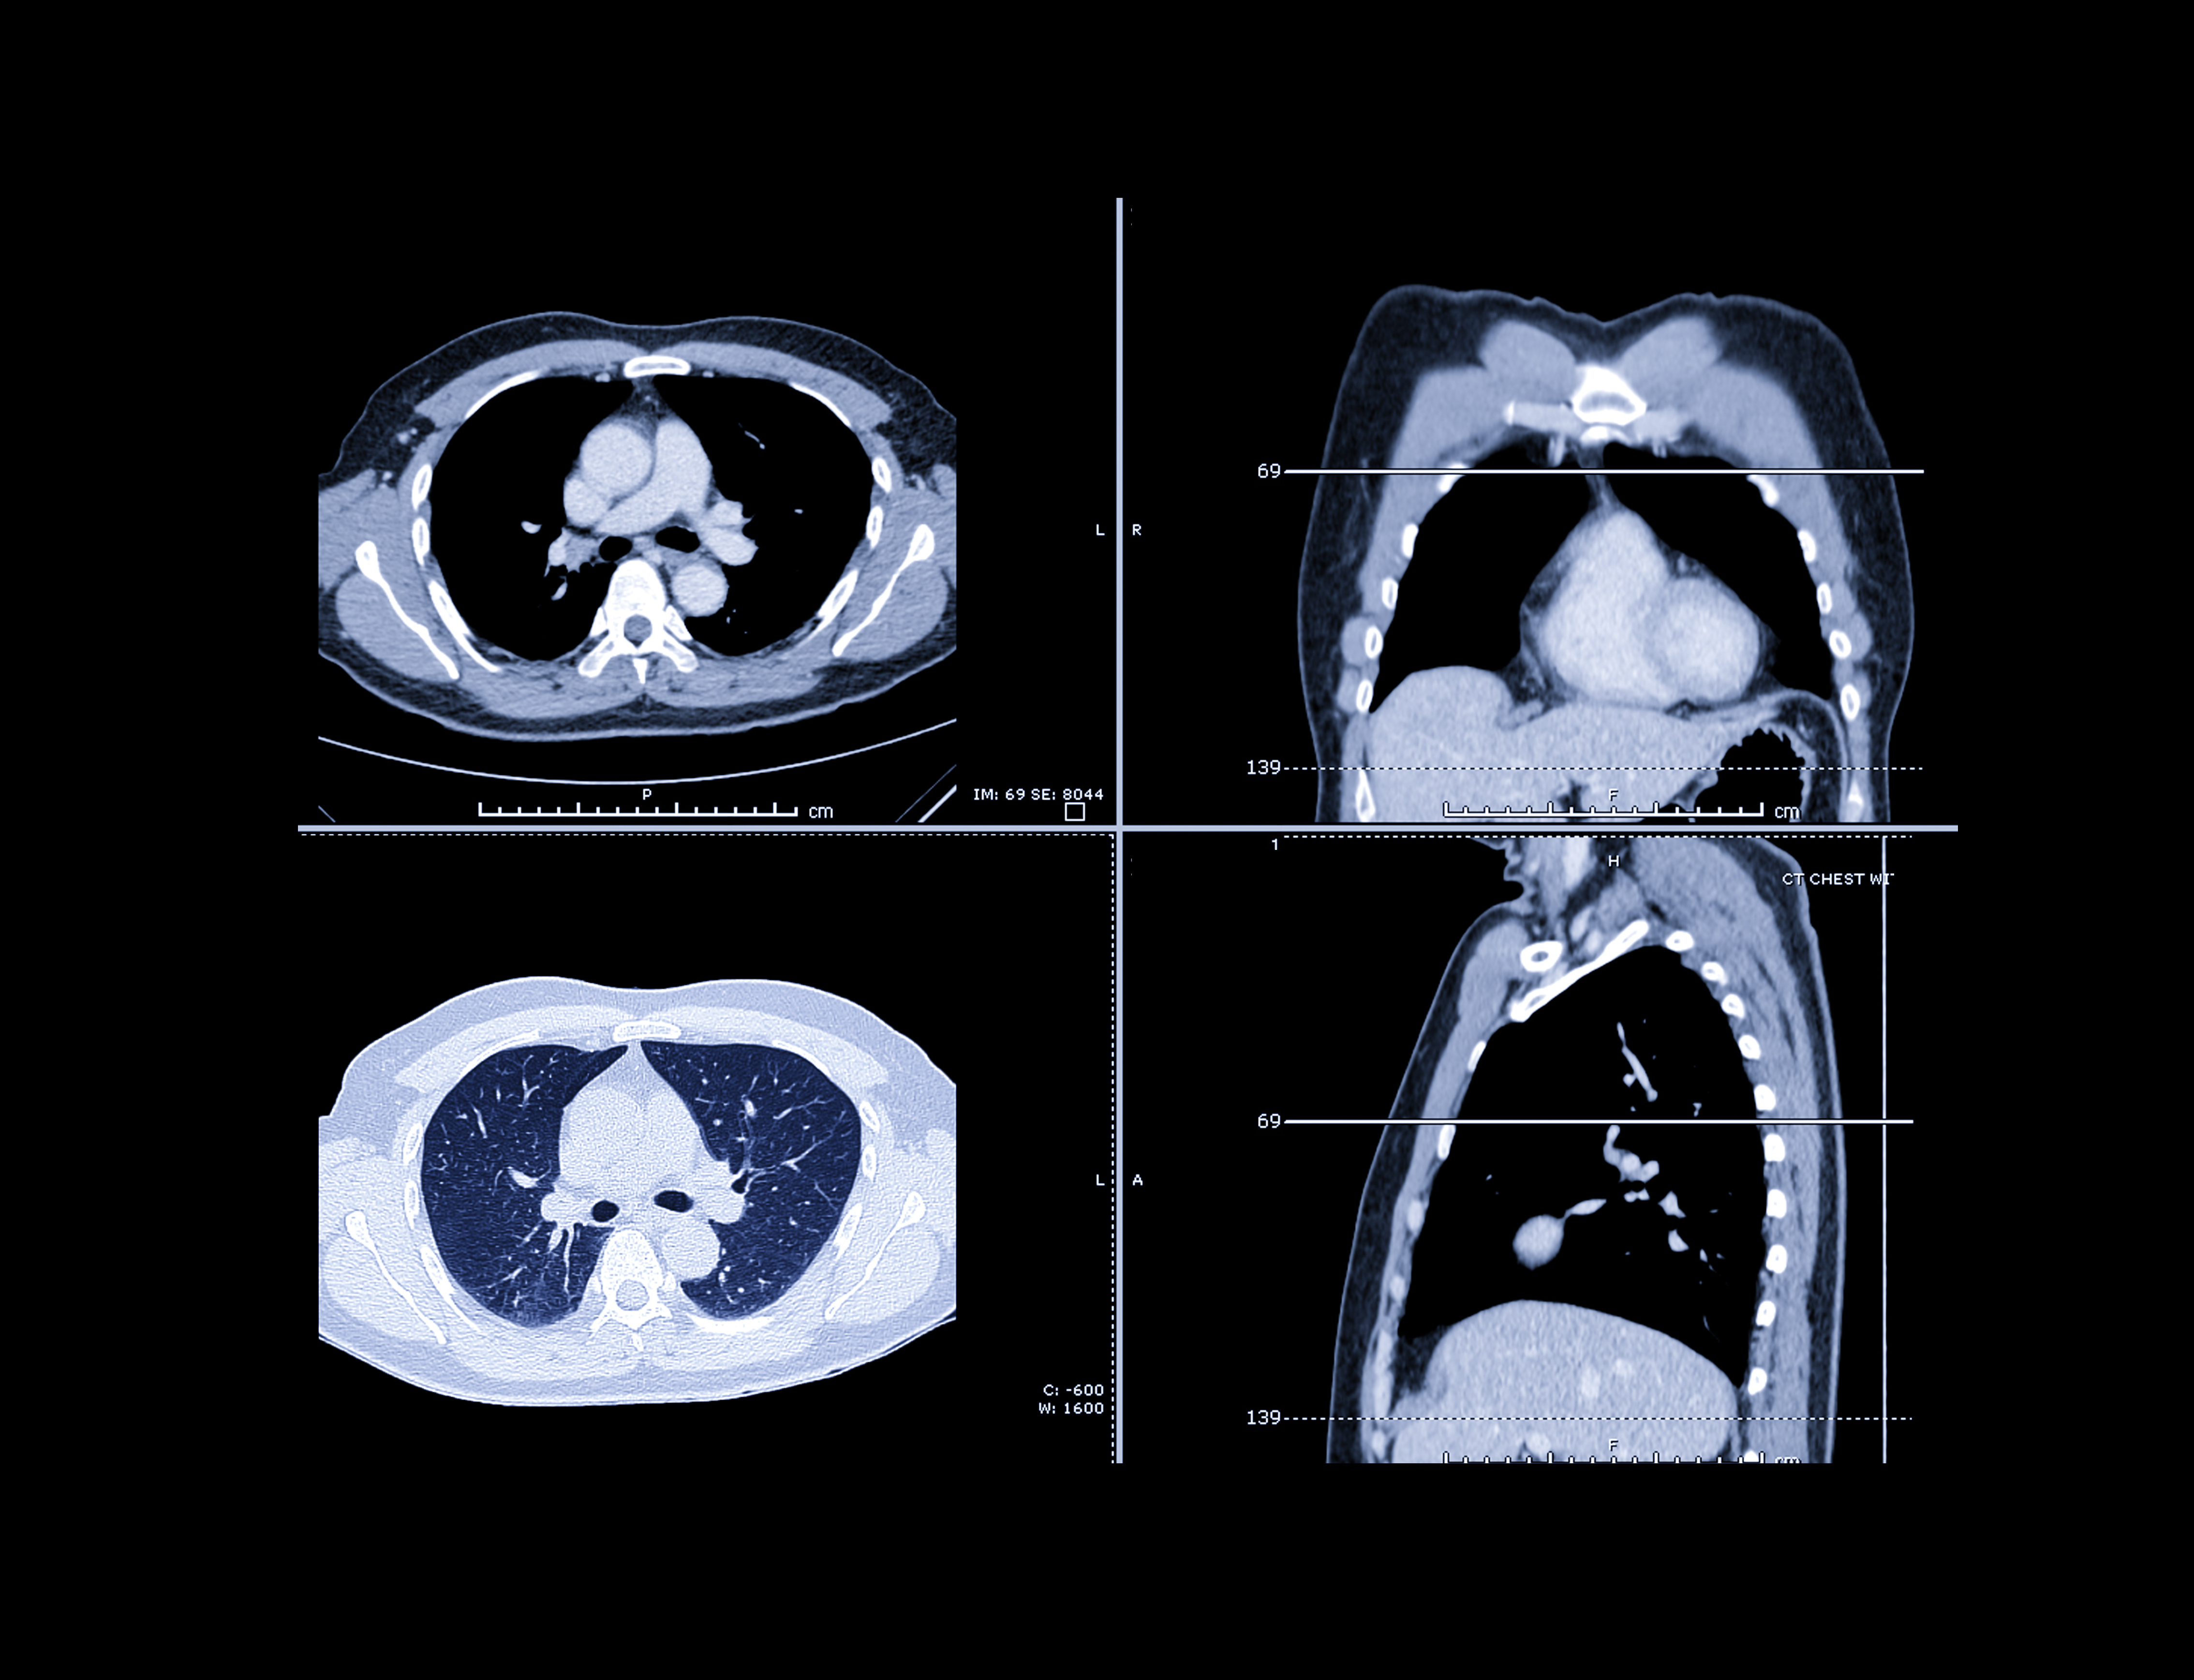

Incidental CT findings -- particularly on lung cancer screening (LCS) -- characterize interstitial lung abnormalities (ILAs) in Asian populations, researchers have reported.

Kim's group investigated the prevalence of ILAs and the association of ILAs with lung cancer, idiopathic pulmonary fibrosis (IPF), and mortality in a Korean cohort, including data from 125,600 individuals who participated in the Korean National Lung Cancer Screening Program between August 2019 and December 2020. The researchers identified ILAs from CT reports and assessed ILA prevalence across age groups. They also calculated incidence rate ratios for lung cancer, IPF, and all-cause mortality in patients with ILAs and those without.